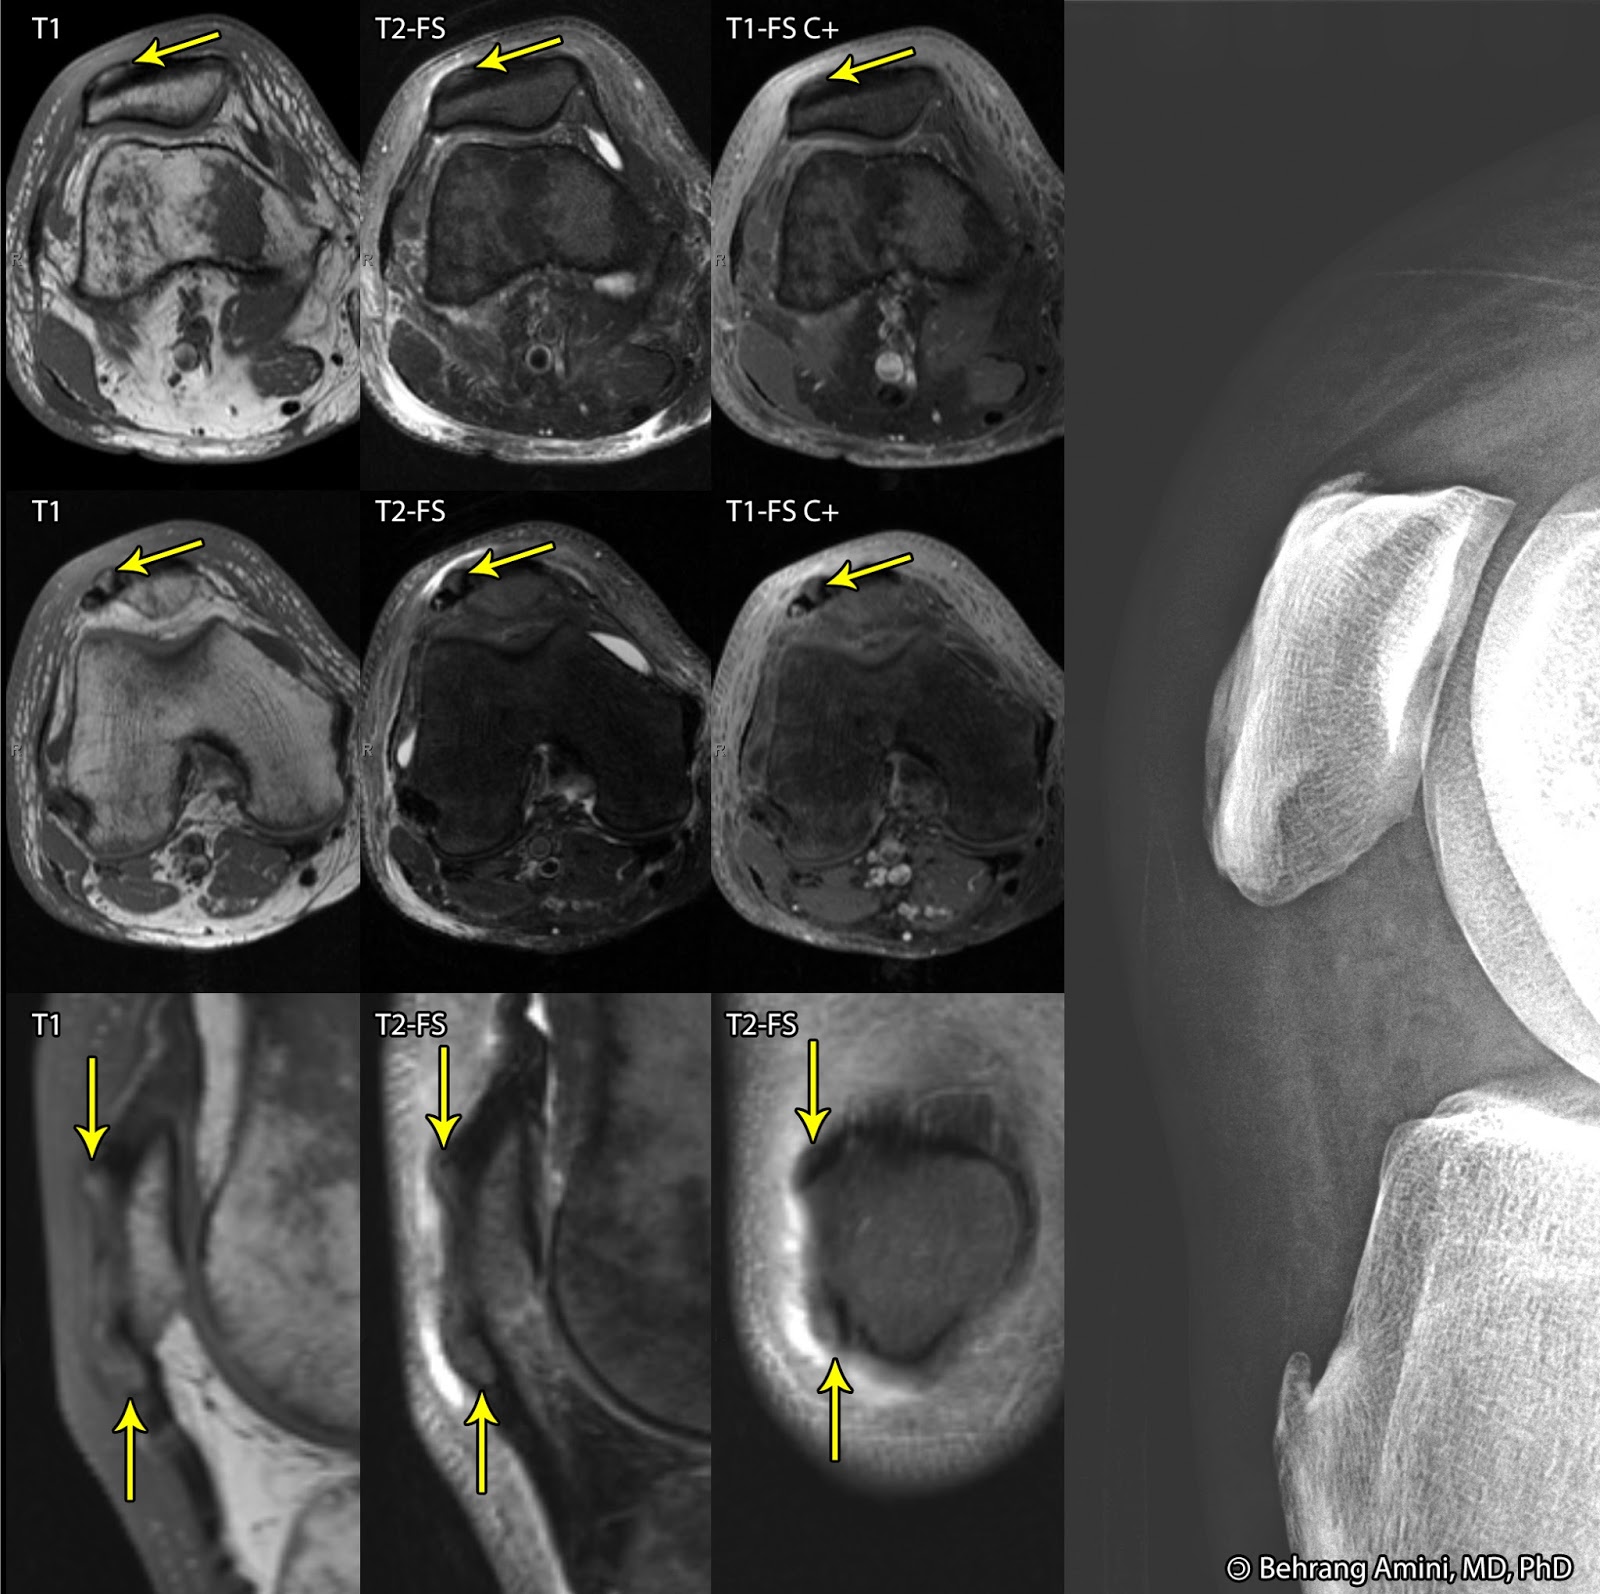

From roentgenrayreader.blogspot.com

Roentgen Ray Reader Gout of the extensor mechanism of the knee Curbsiders Gout Learn from expert tuhina neogi md, phd how to diagnose gout with or without arthrocentesis, how to treat flares, and how to counsel patients with firefighting and. Learn from expert tuhina neogi md, phd how to initiate and titrate urate lowering therapy, guidelines controversy over uric acid. How to initiate and titrate urate lowering therapy, guidelines controversy over uric acid. Curbsiders Gout.